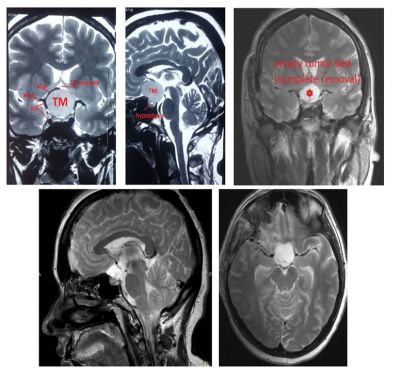

Mediainfo.az-a nazirlikdən verilən məlumata görə, Qadın Respublika Müalicəvi Diaqnostika Mərkəzinə (RMDM) müraciət edib, çəkilən baş beyin MRT-də görmə çarpazını, hipotalamusu, beynin əsas damarlarını sıxan böyük ölçülü (4 sm) törəmə aşkar edilib.

RMDM-in neyrocərrahı Azər Əkbərov tərəfindən aparılan əməliyyat nəticəsində sağ pterional kraniotomiyadan törəmə tam xaric edilib.

Önəmli strukturların hamısı qorunub. Bir neçə saatdan sonra xəstə sağ gözü ilə işığı seçməyə başlayıb, sol gözdə 1,5 metrdən barmaq sayılacaq qədər görməsi artıb.